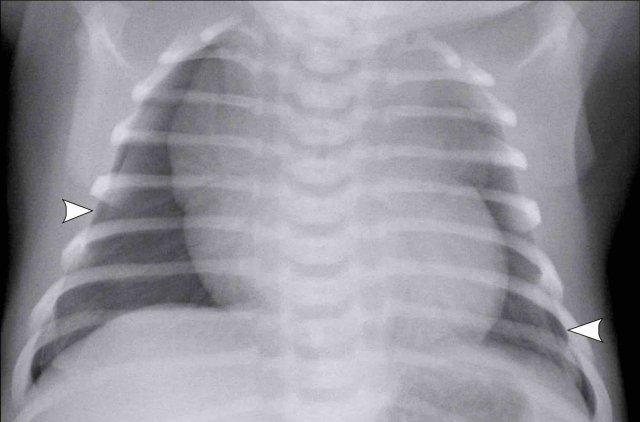

Trẻ sơ sinh đủ tháng, 2 giờ sau sinh mổ chủ động với một số dấu hiệu suy hô hấp.

Image

- Mild

hyperinflation - Subtle

interstitial linings on both sides - Some pleural

fluid on the right side (arrow). - Skin fold on the right

side

Sau

liệu pháp hỗ trợ, tình trạng suy hô hấp đã biến mất vào ngày hôm sau.